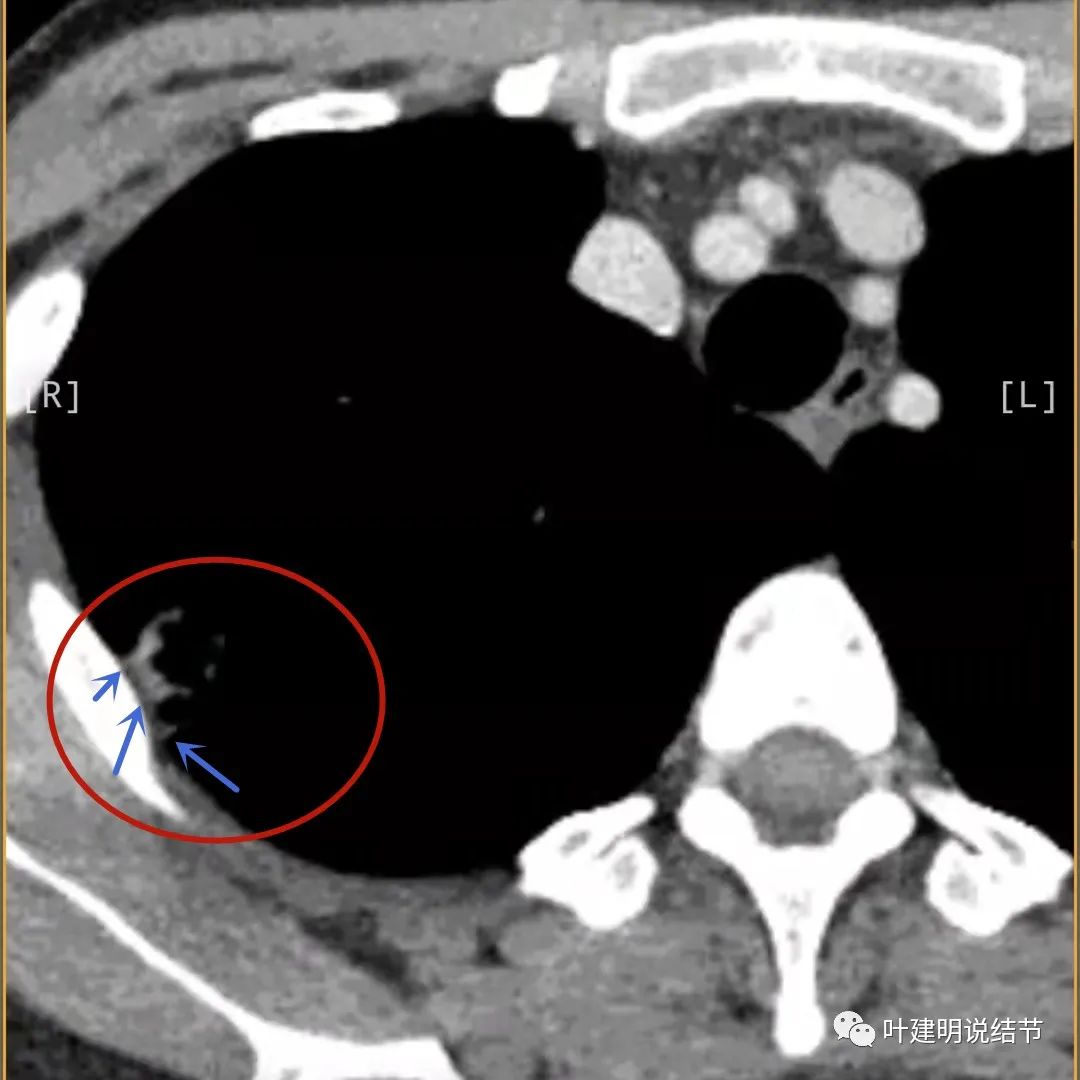

邻近胸膜有增厚(蓝色箭头),主病灶边缘较为平直,缺乏膨胀性(桔色箭头),实性部分密度过高(粉色箭头),旁边有磨玻璃影,散且模糊(砖色箭头)

病灶边缘较为平直,膨胀性不足(桔色箭头)